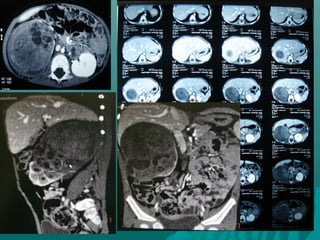

TEM DE ABDOMENTEM DE ABDOMEN

PROTOCOLO PARA TEM DEPROTOCOLO PARA TEM DE

ABDOMENABDOMEN

 MODO ESPIRAL PARA RUTINA DELMODO ESPIRAL PARA RUTINA DEL

ABDOMEN DE NEONATO VG.ABDOMEN DE NEONATO VG.

 TUMORES, ANORMALIDADES,TUMORES, ANORMALIDADES,

MALFORMACIONES ,ABSCESOS ETC.MALFORMACIONES ,ABSCESOS ETC.

TUMOR DE WILLSTUMOR DE WILLS

HIDRONEFROSIS BILATERALHIDRONEFROSIS BILATERAL

FIBROQUISTOSIS RENALFIBROQUISTOSIS RENAL